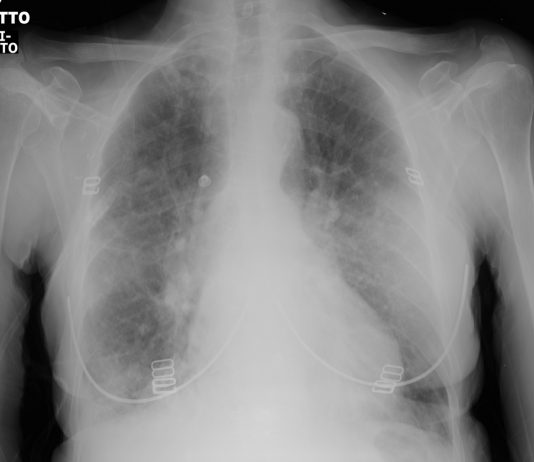

46-year-old asymptomatic female patient underwent chest radiography followed by CT since her husband was diagnosed of Covid-19 pneumonia (case n 14). pO2: 98%.

Chest radiography